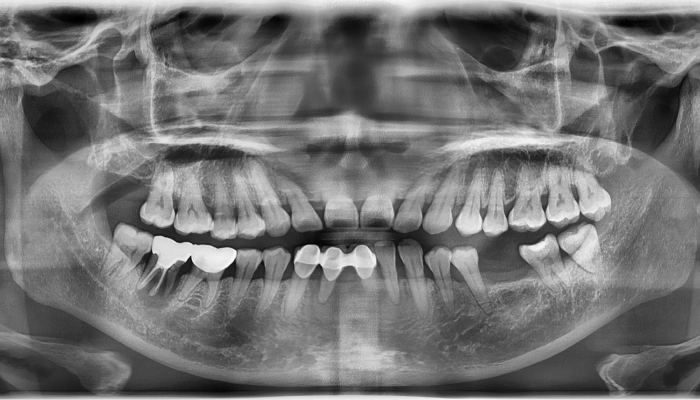

• 식립 전

식립 후